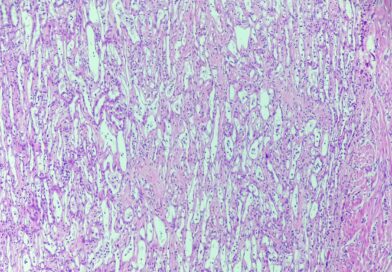

Przypadek 357. Szkoły Młodych Patologów.

Pacjentka 45 letnia z nawracającymi krwawieniami z macicy i rozpoznanymi w USG licznymi guzkami trzonu macicy. W trybie planowym usunięto